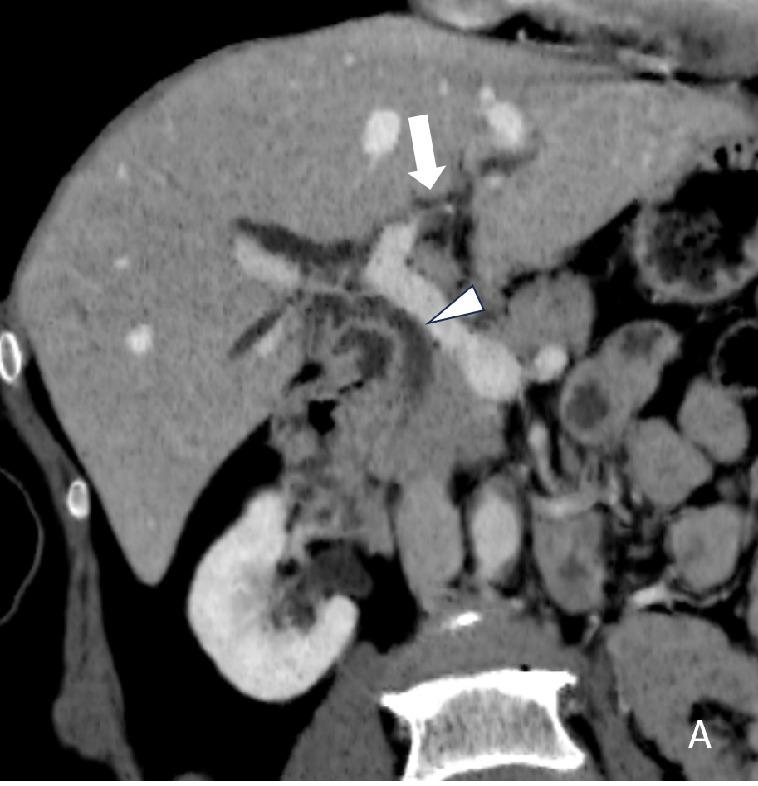

The study population was 4,337 villagers in Northern Thailand with a 5-year abdominal US surveillance. Patient demographics data and ultrasound findings of calcifications/granulomas, periductal fibrosis, and diffuse bile duct dilatation were included. A logistic regression model was used to determine significant predictors.

There were 4,225 people included with an average age of 45.49±7.66 years. Prevalence of calcifications/granulomas, periductal fibrosis, and diffuse bile duct dilatation detected on baseline sonographic surveillance was 11.7%, 20.5%, and 11.3%, respectively. The univariate analysis for significant predictors for CCA include age (Relative Risk; RR = 1.12), family history of CCA (RR = 2.29), periductal fibrosis (RR=2.38), and diffuse bile duct dilatation  (RR = 7.59). The multivariate analysis the independent predictors were age (RR = 1.12), family history of CCA (RR = 1.92), and diffuse bile duct dilatation (RR = 5.94), respectively.

The sonographic predictor for CCA surveillance in endemic areas is diffuse bile duct dilatation.  Age and family history of CCA are also helpful clinical markers.